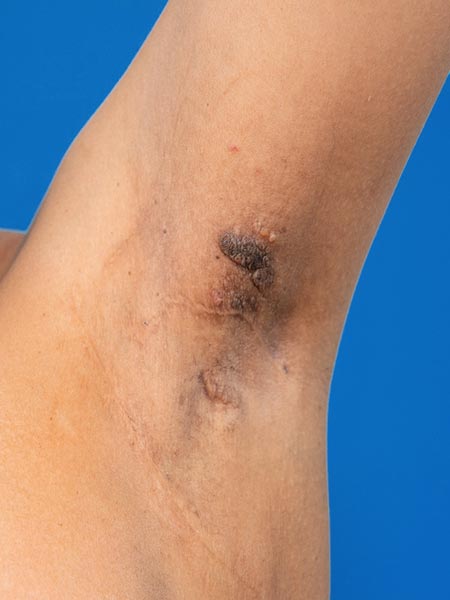

The patient suffers from a constant, blood-tinged lymph outflow in the left axilla. Approximately 500 ml of fluid (lymph with blood) leaks per day from the small cutaneous lymphatic vesicles, some of which are also exophytic (“lymphangioma circumscriptum”).

Photograph of clinical control 3.5 months after bleomycin electrosclerotherapy (BEST). The lesion has become much smaller. There is no longer any fluid secretion, the axilla is dry.